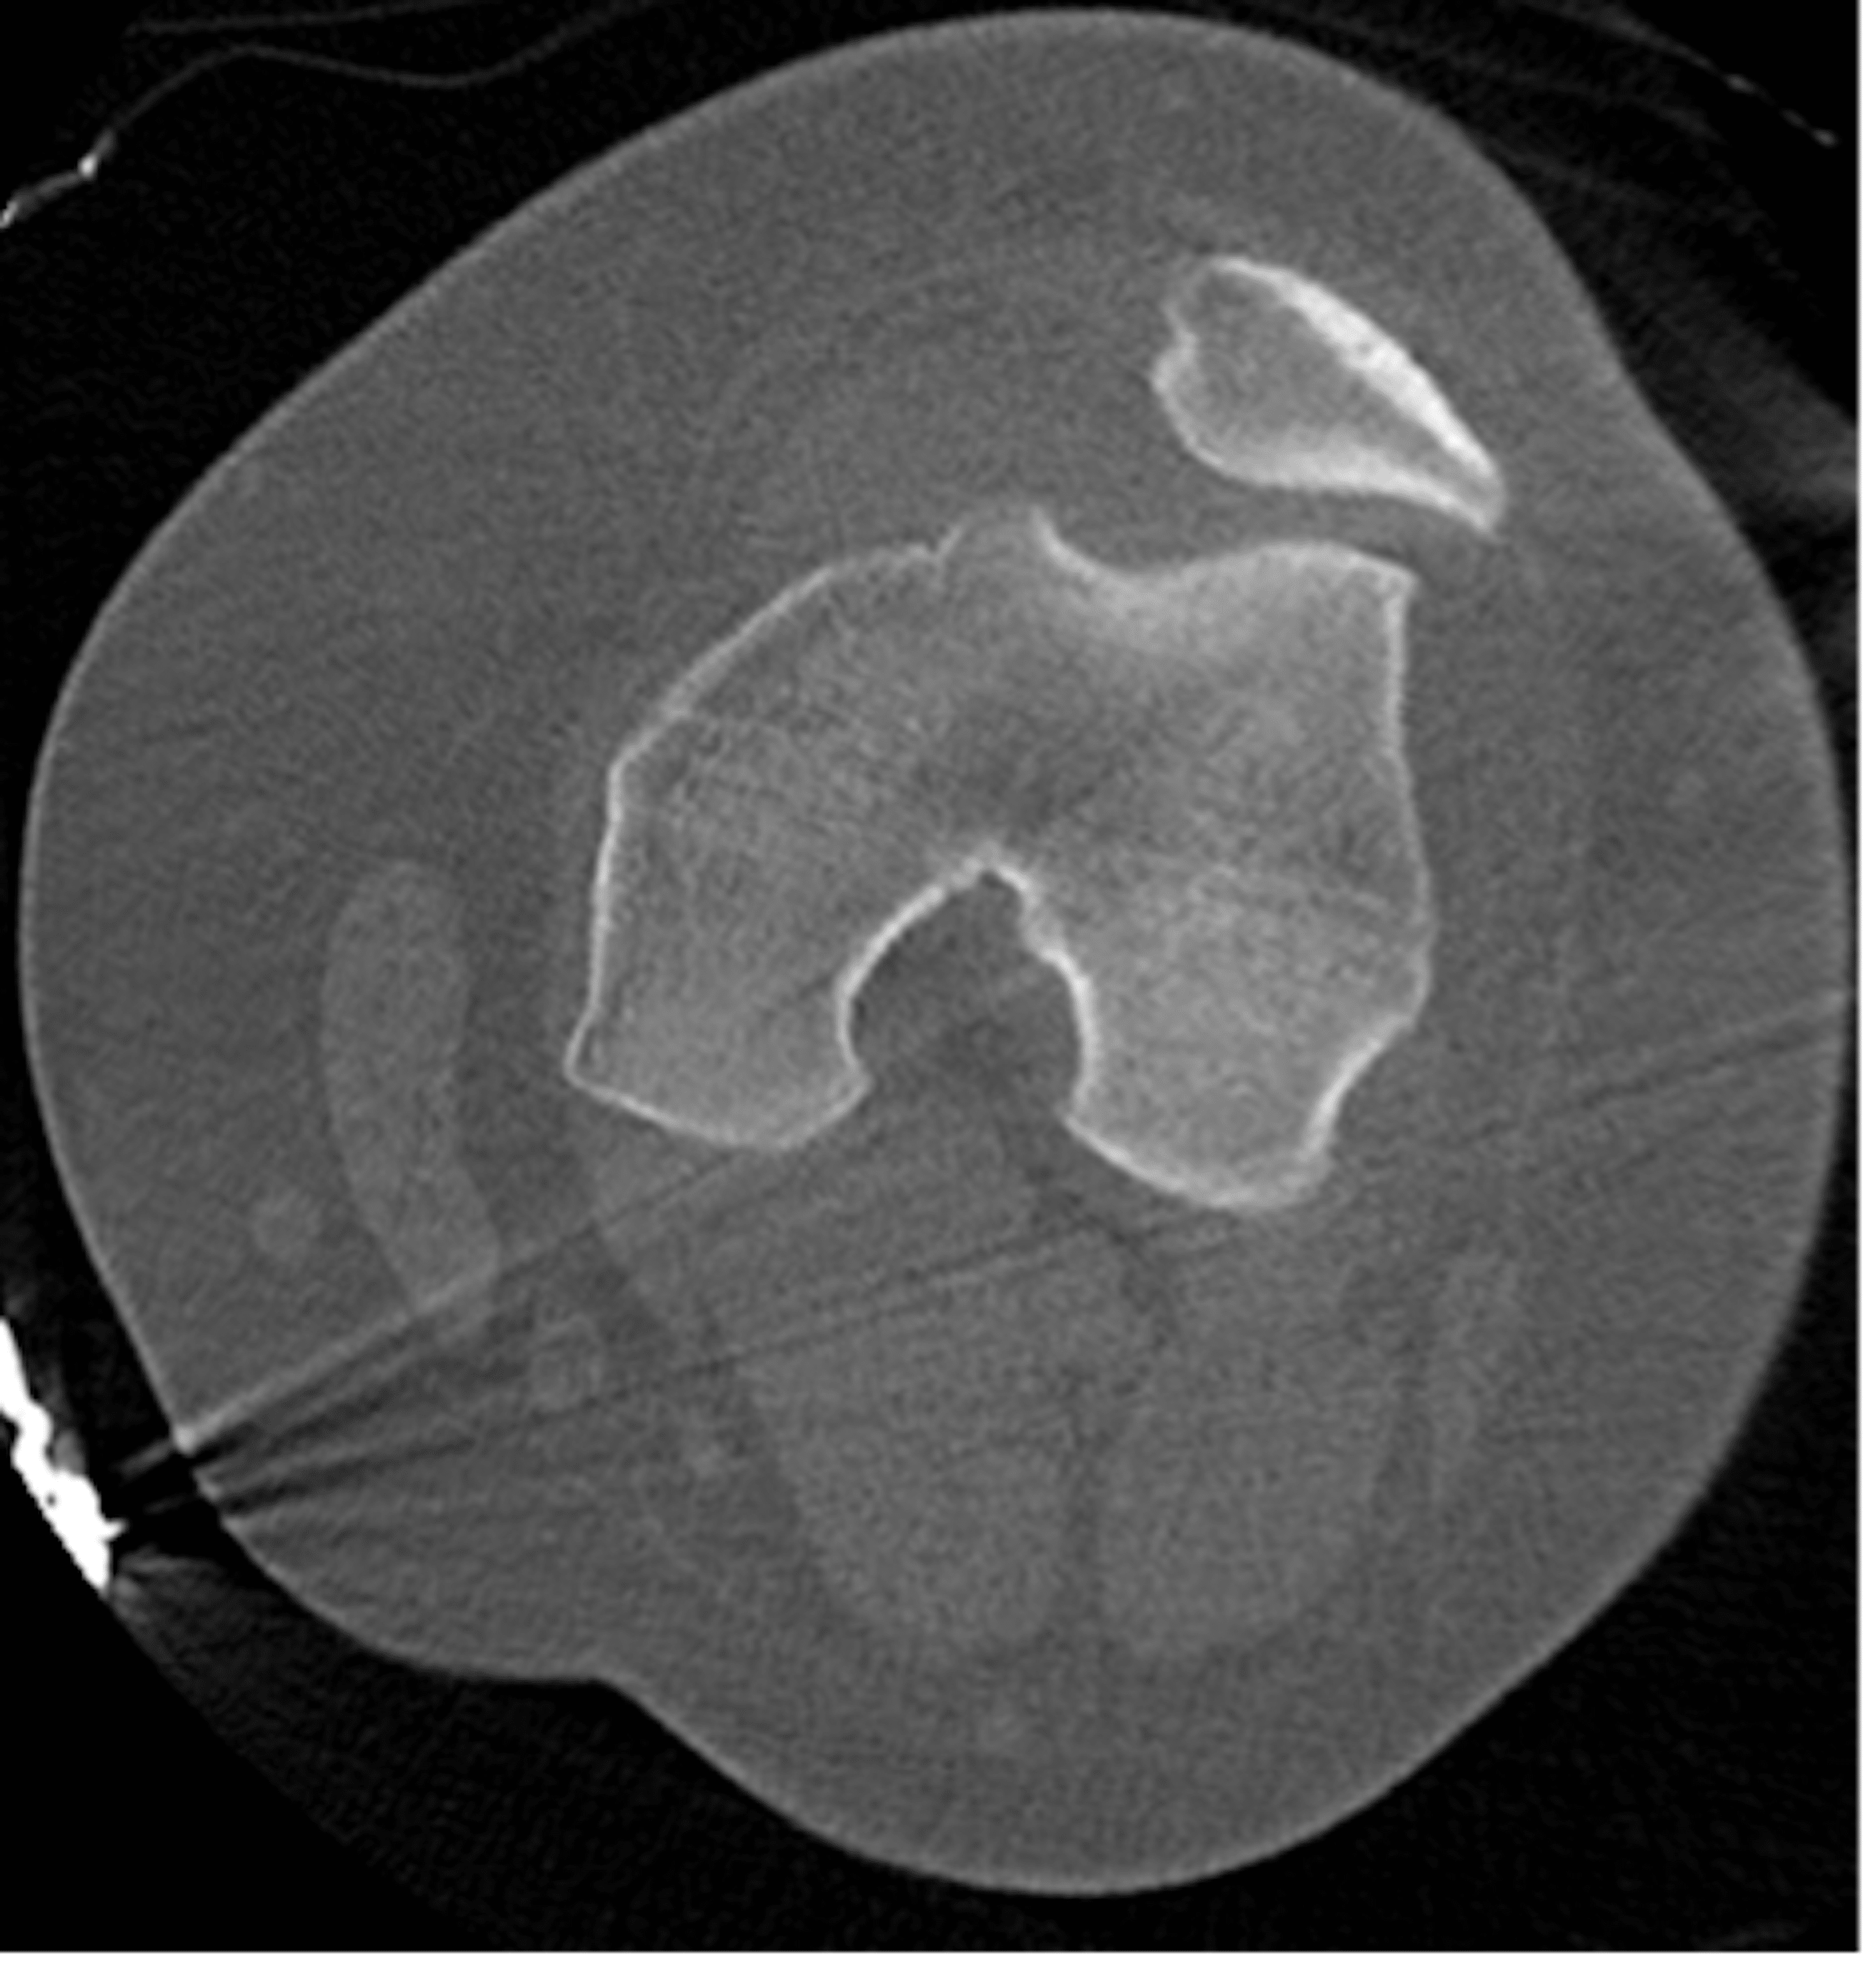

From www.thelancet.com

Pain, popping, and episodic locking of the knee osteochondromatosis Locked Knee Reduction the acute locked knee is an orthopaedic emergency requiring prompt diagnosis and treatment. It can be classified as acute or. if knee pain is the cause for a locked knee, the goal of treatment will be pain control and reducing inflammation. Find out about the common causes of a knee. a true knee lock occurs when something. Locked Knee Reduction.